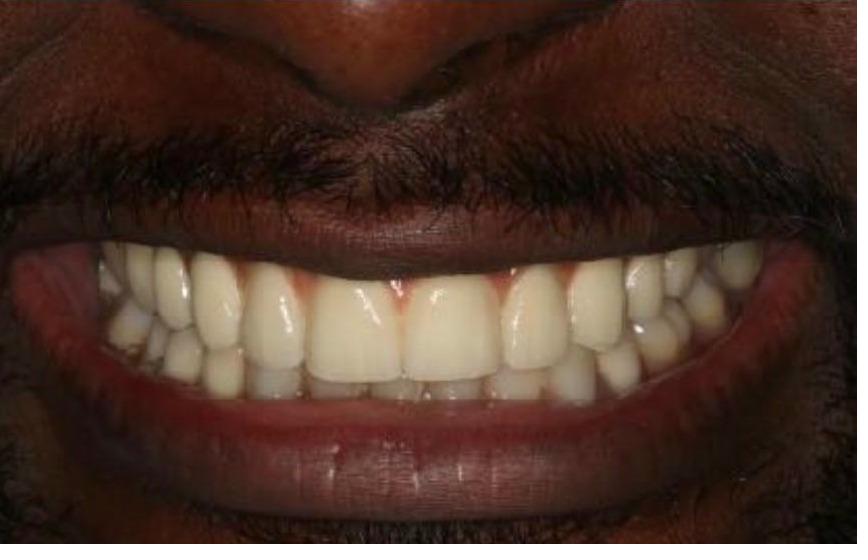

To improve this patient's esthetics, he first had orthodontics to properly align the teeth followed by bleaching. I then replaced the old crowns on his two front teeth with new ceramic crowns to improve the color, contour and esthetics. He was extremely happy with his new smile.

This patient had significant wear and chipping of his teeth. To restore his dental esthetics and function, following orthodontic therapy I fabricated crowns for his front teeth to restore the proper length, contour, and esthetics. He was thrilled with the result of our interdisciplinary care.

To improve this patient's esthetics, after orthodontic treatment we bleached his teeth to brighten his smile. Once we achieved the desired shade I fabricated new crowns to match his other teeth. He was extremely happy with the result!